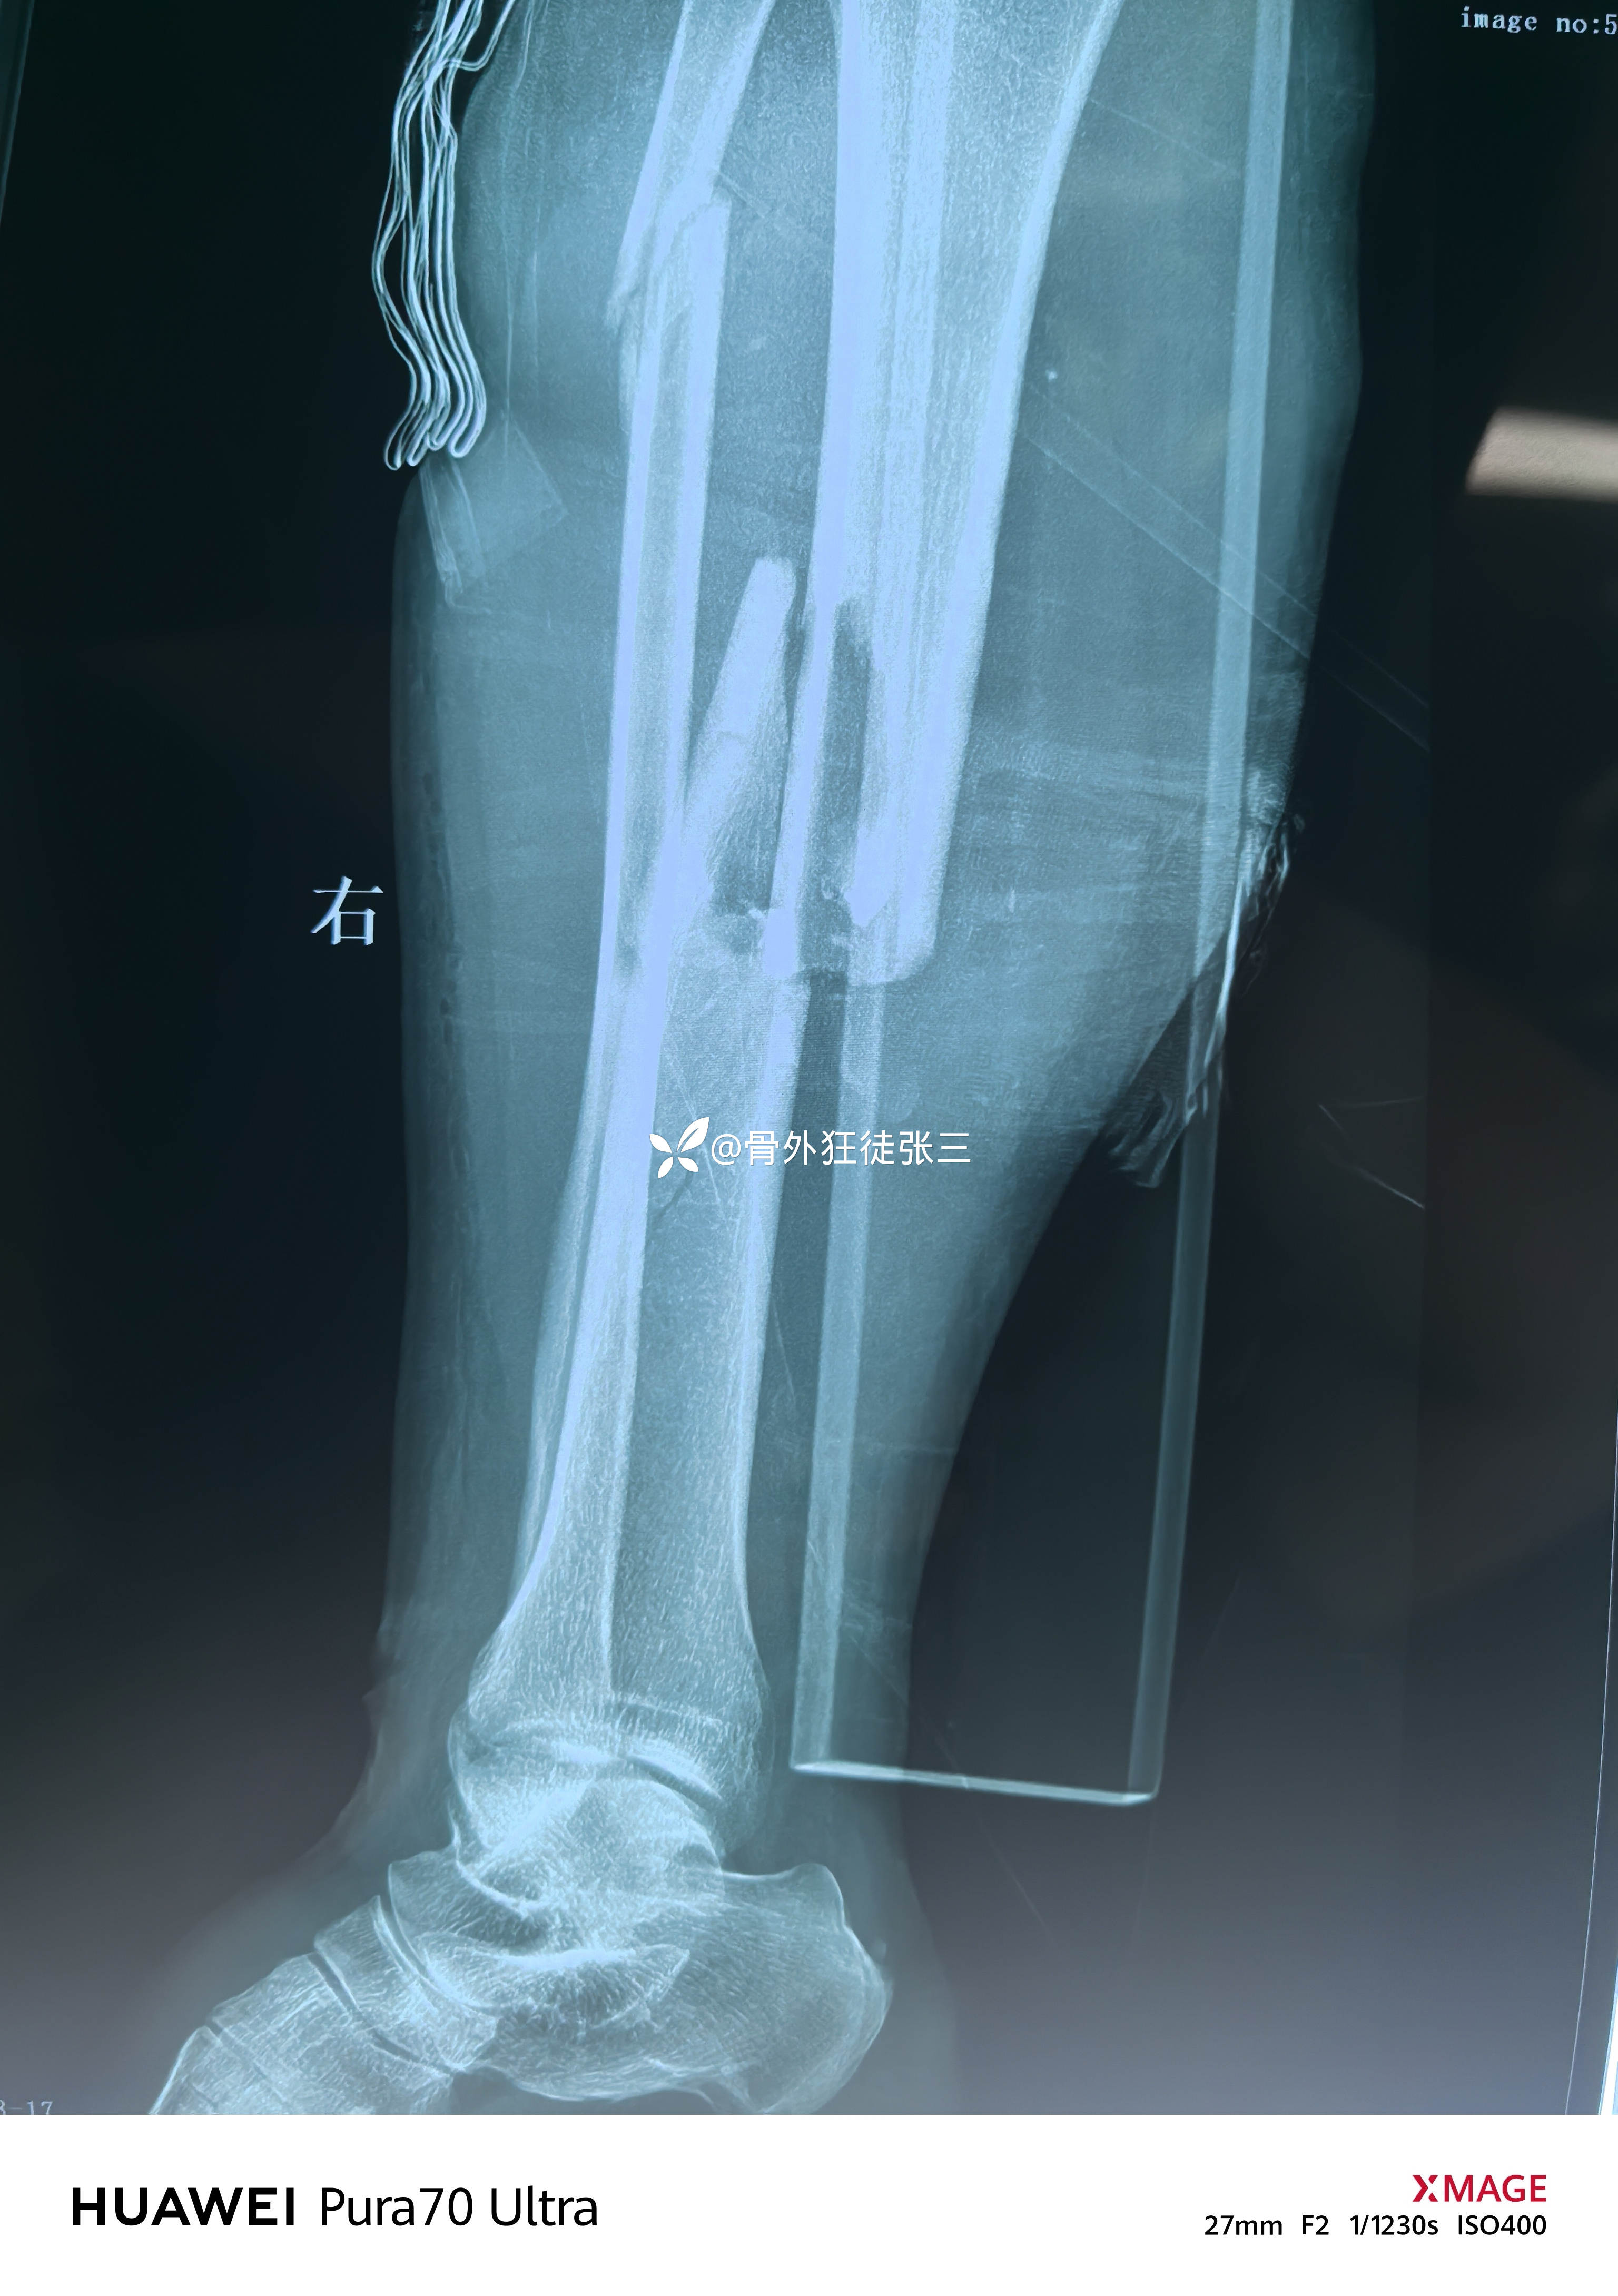

左胫腓骨开放性骨折伴皮肤撕脱、缺损

单边外架临时固定

3,胫骨外固定架是否可以调整后终极固定?或者更换为内固定时机?